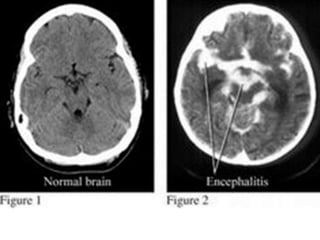

Encephalitis

•sleepy sickness, or sleeping sickness

•severely reducing their ability to

produce the chemical nerve impulse

transmitter dopamine

Encephalitis •sleepy sickness, orsleeping sickness •severely reducing their ability to produce the chemical nerve impulse transmitter dopamine